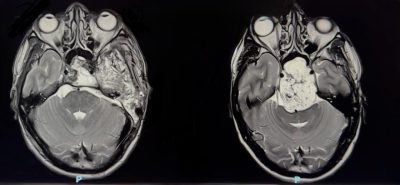

نجح فريق طبي سعودي في مستشفى الملك فهد بجدة عضو تجمع جدة الصحي الثاني بقيادة د. هاني القرشي في استئصال ورم حبلي نادر ومعقد من قاع الجمجمة، خلال ثلاث عمليات جراحية متتالية استغرقت ٣٥ ساعة. الورم كان ضاغطًا على جذع الدماغ والأعصاب القحفية، وتعامل معه الفريق بتقنيات جراحية متقدمة لا تُجرى إلا في مراكز عالمية محدودة، ولله الحمد المريض تعافى وعاد لحياته الطبيعية دون أي عجز عصبي يذكر.